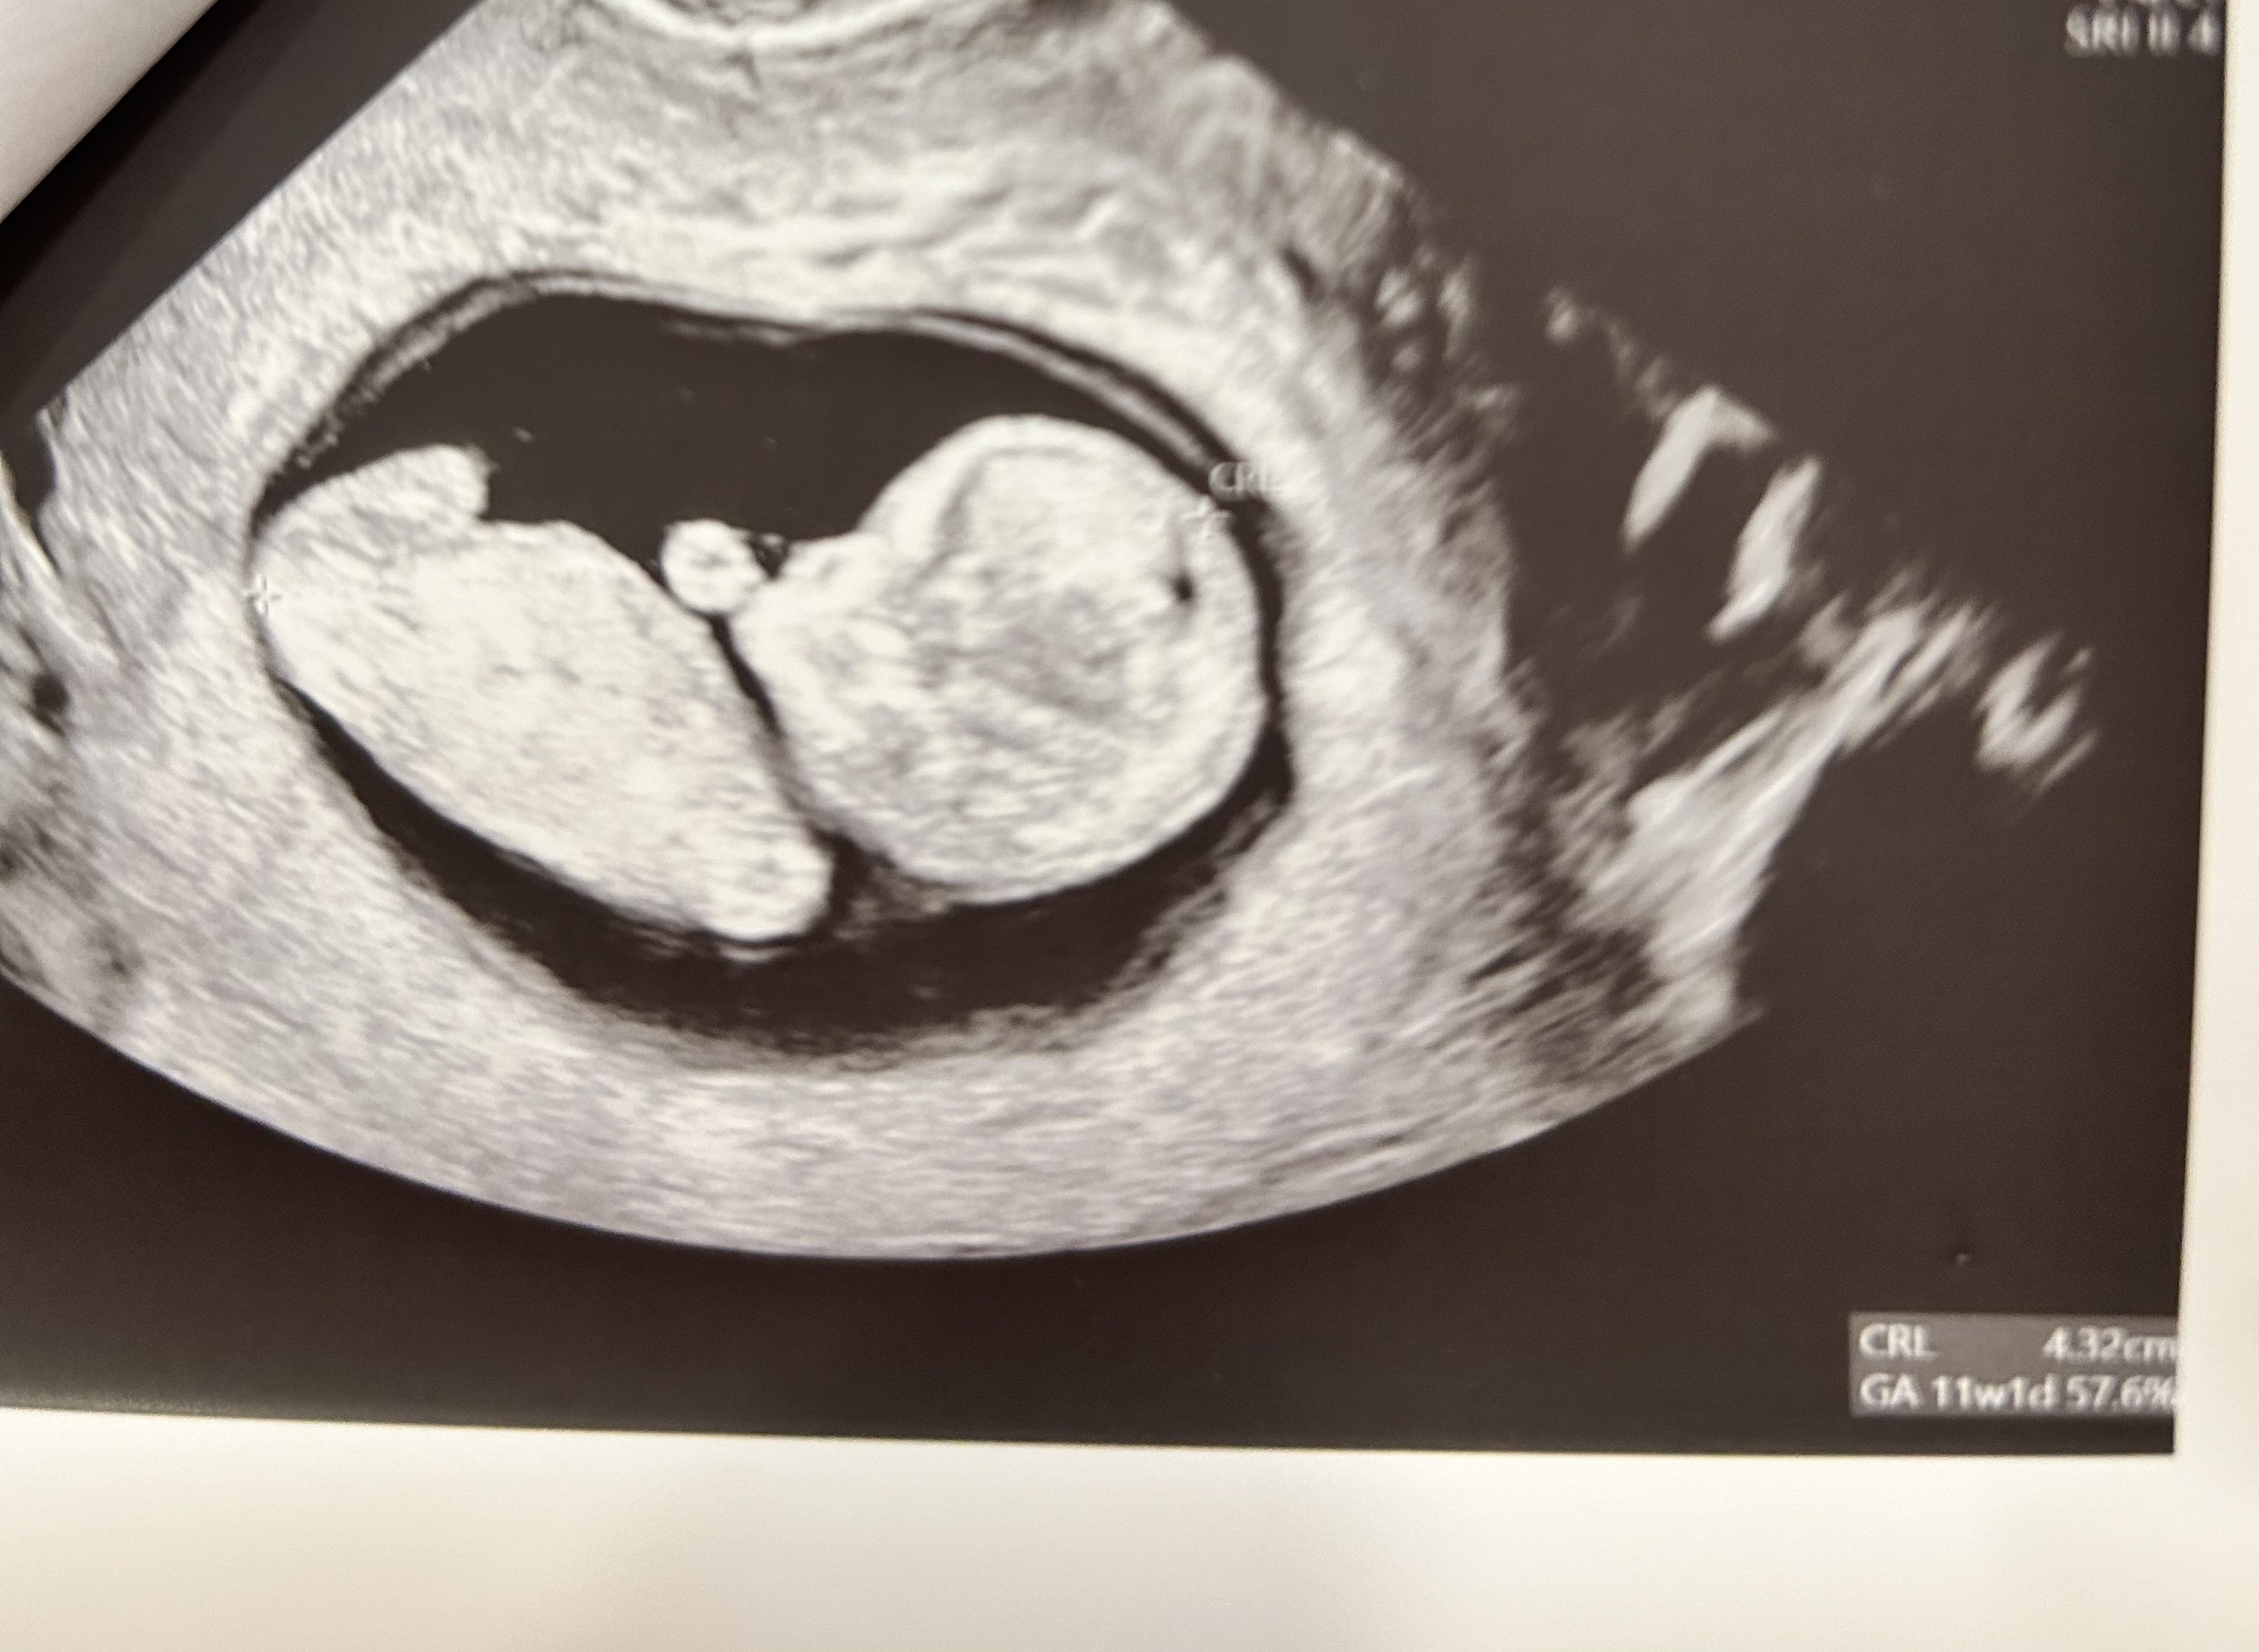

Jaki to jest piękny widokMi się pomyliło, myślałam że czwarty grudnia to czwartek, wizytę miałam dzisiaj.

Ciągle inne pomiary ale to chyba normalne na tym etapie?bo równo dwa tygodnie temu miało być 8+4, było 8+6. Dzis powinno być 10+6 a 11+1.

Krwiaka ani śladua jak lekarz pokazał monitor to aż krzyknęłam:” ale duży”

Normalnie to człowieczek, widać główkę, ręce nogi i się ruszałi przekręcił z brzucha na plecy

do teraz jestem w szoku jak to wygląda

Ale cudny widokMi się pomyliło, myślałam że czwarty grudnia to czwartek, wizytę miałam dzisiaj.